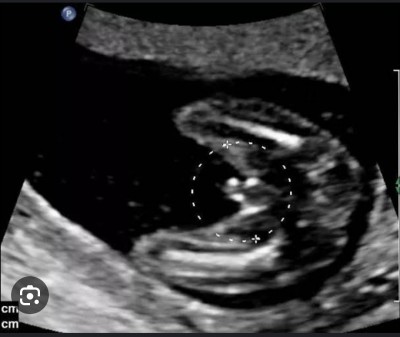

Tecrübeli anneler bebişime doktor 11.14 haftalarda hep erkek dedi 16 da kız dedi 19 da dün gittim kız dedi ama başta erkek dediği için güvensizlik oldu bacak arası net görüntüsünü ekleyeceğim anlayanlar bakabilir mi? Ortada ufak bi şey var o ney ?

Gebelik haftası 19

Kız bebek muhtemelen çünkü arada boşluk var

Çıkıntısı yok canım hem bu haftalarda yanılma olmaz kesin kızdır

Olsa belli olurdu benmli 12+4 de erkek olduğunda bu kadrdi cikintisi seninki19 olmus cok belirgin olurdu pipisi cnm kiz seninki

Ortadaki minik şey nedir peki

kızlarda oluyor çünkü 19 haftaddasiniz şimdiye baya baya belirgin olmustu eyer erkek olsaydu

Yüzde yüz kiz cnm benim o küçük çıkıntı kızlarda olan bişey

O minik ortadaki şey ne peki

Minik o çıkıntı klitoris oluyor muş.Dr. öyle anlattı erkek deyip kiz çıkanlar var dedim Dr.  Sağolsun tüm detayları anlattı bana bazen kız çocuklarında ödem oluyor  şişlik oluyor dedi erkek sanıyoruz dedi.yanilmalar ondan kaynaklı dedi.

Rabbim analı babalı büyütsün inşallah... Prenses geliyor.. Bacak arasında 3 çizgi var..

O bacak arasındaki üç çizgi mi oluyor

Evet